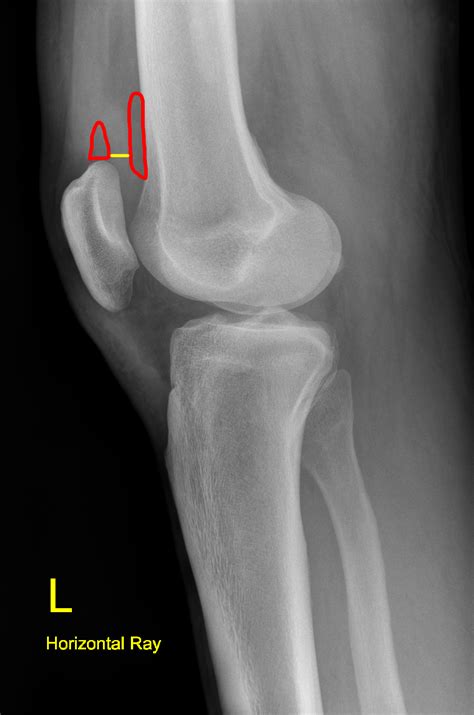

• Imaging Tests: X-rays, MRI, or ultrasound may be used to visualize the joint and assess the extent of fluid buildup.

• Joint Aspiration: In some cases, a needle may be used to remove a sample of the fluid from the joint for laboratory analysis. This can help identify the underlying cause of the effusion.

🔍 Note: Joint aspiration is a minimally invasive procedure that can provide valuable information about the cause of joint effusion. It is typically performed under local anesthesia to minimize discomfort.